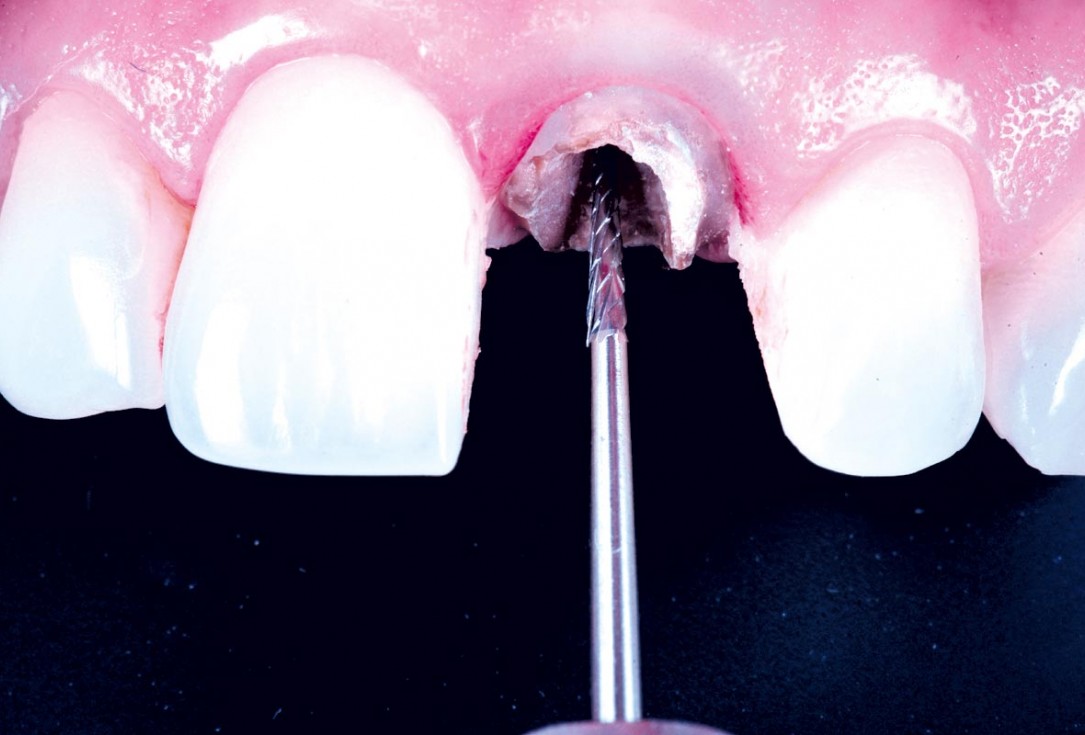

05/30 - Separation with turbine drillExcellent aesthetic result of buccal augmentation with mucoderm® and maxgraft® after immediate implant placement - 3-years follow-up - Dr. A. Puišys